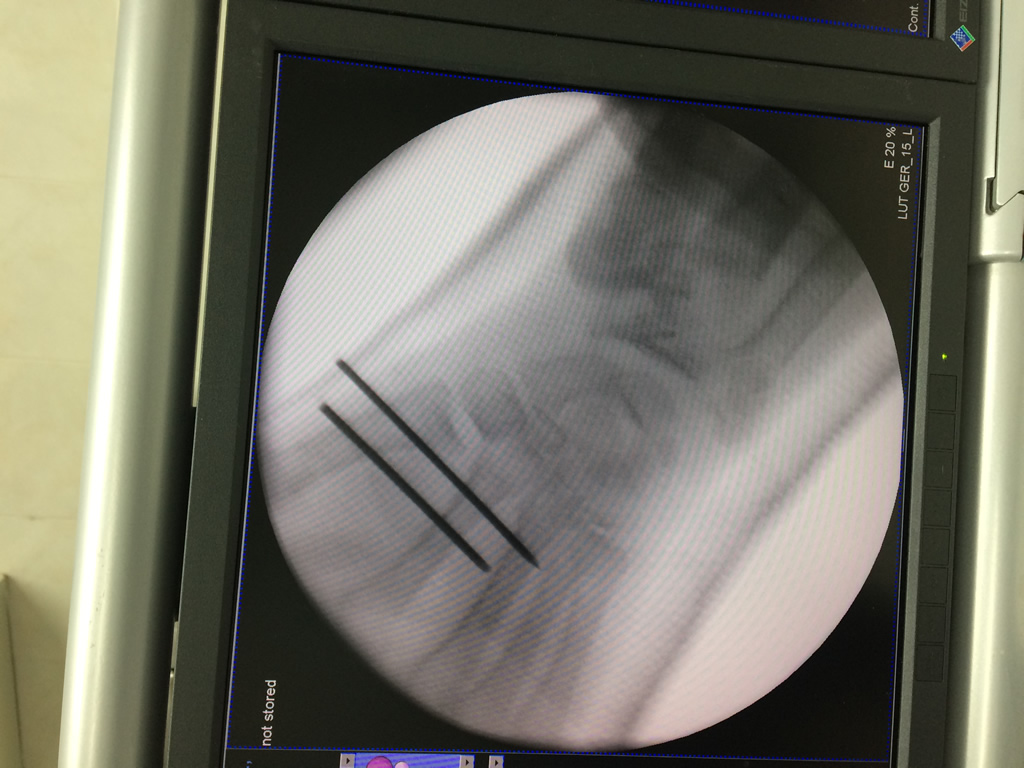

Cirugías de Peroné y Tibia

Los procedimientos más comunes en cirugía de la mano son aquellos destinados a reparar traumatismos, incluyendo lesiones de tendones, nervios, vasos sanguíneos, y articulaciones; huesos fracturados; y quemaduras, cortes, y otros daños de la piel.